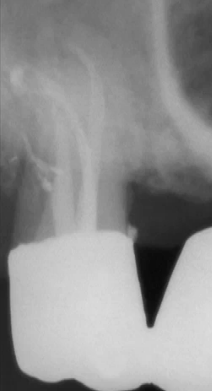

Se realiza con un cemento sellador y conos de gutapercha. Se

ubica un cono de gutapercha acorde al diámetro del instrumento

que ha mecanizado la zona apical, en este caso fue una lima Nº

25. Ver imagen derecha (1)

El cono maestro Nº 25 se embadurna con el cemento sellador y

se lo hace llegar hasta el fondo del ápice, luego con un

espaciador digital Nº 25 se presiona hacia el fondo y contra las

paredes del conducto (2), con esto se logra una

condensación lateral para que el cemento sellador penetre el

delta apical y conductos accesorios (3)